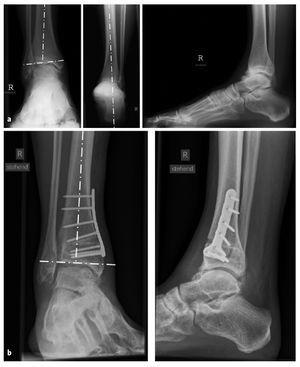

Figuras 14a y 14b. a) Radiografía de un paciente varón de 29 años con una desviación en varo aislada de la articulación tibiotarsiana, que también se observa en la lateralización de la radiografía de Saltzman. b) Radiografías 3 meses después de la osteotomía en cuña abierta medial de la tibia distal con normalización del ángulo de la articulación tibiotalar.